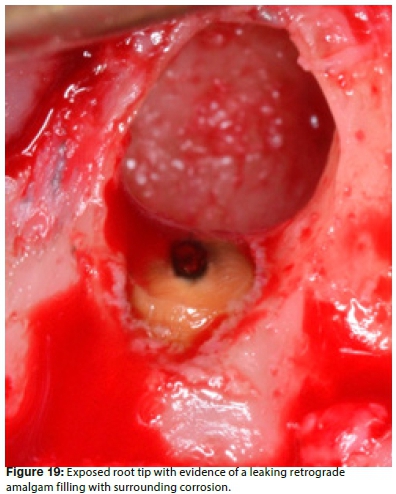

Periradicular curettage was done with a periodontal curette to remove the tissue for biopsy and to expose the root apex. Figure 19 shows the exposed root tip with evidence of a leaking retrograde amalgam filling with surrounding corrosion, at the apex of the root tip. Several studies indicate that amalgam retrograde performs consistently the poorest in leakage studies.36,37 According to Carr and Castellucci (2009) there is no longer any valid reason for using amalgam as a retrograde filling material due to the general controversy over the presence of mercury in amalgam.18 Furthermore, amalgam is prone to corrosion and disintegration, can cause amalgam tattooing if excess particles are incorporated into the soft tissue, and the healing characteristics following an amalgam root-end filling are questionable.7,32